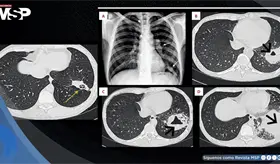

El estudio histológico confirmó un adenocarcinoma mucinoso de células en anillo de sello de vejiga con invasión muscular y diseminación metastásica pulmonar y ósea.